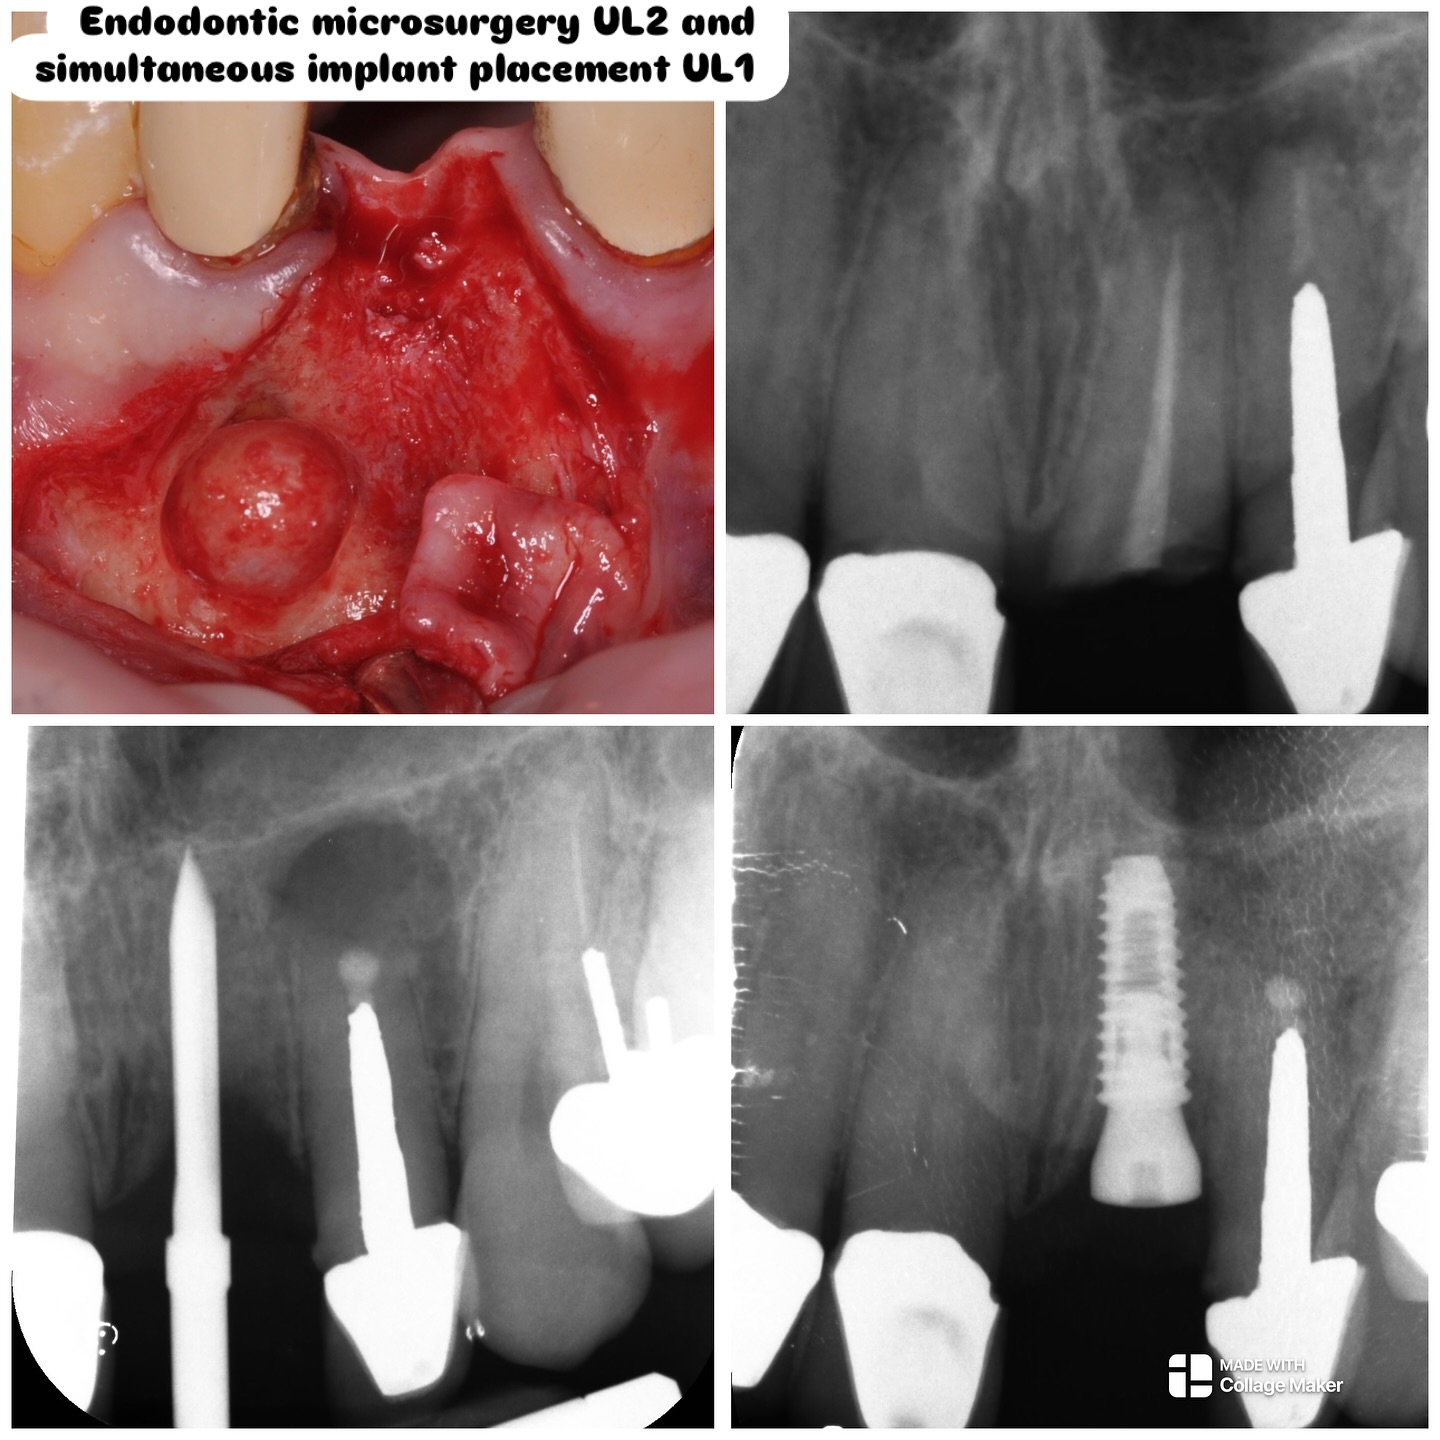

Operative microscopy